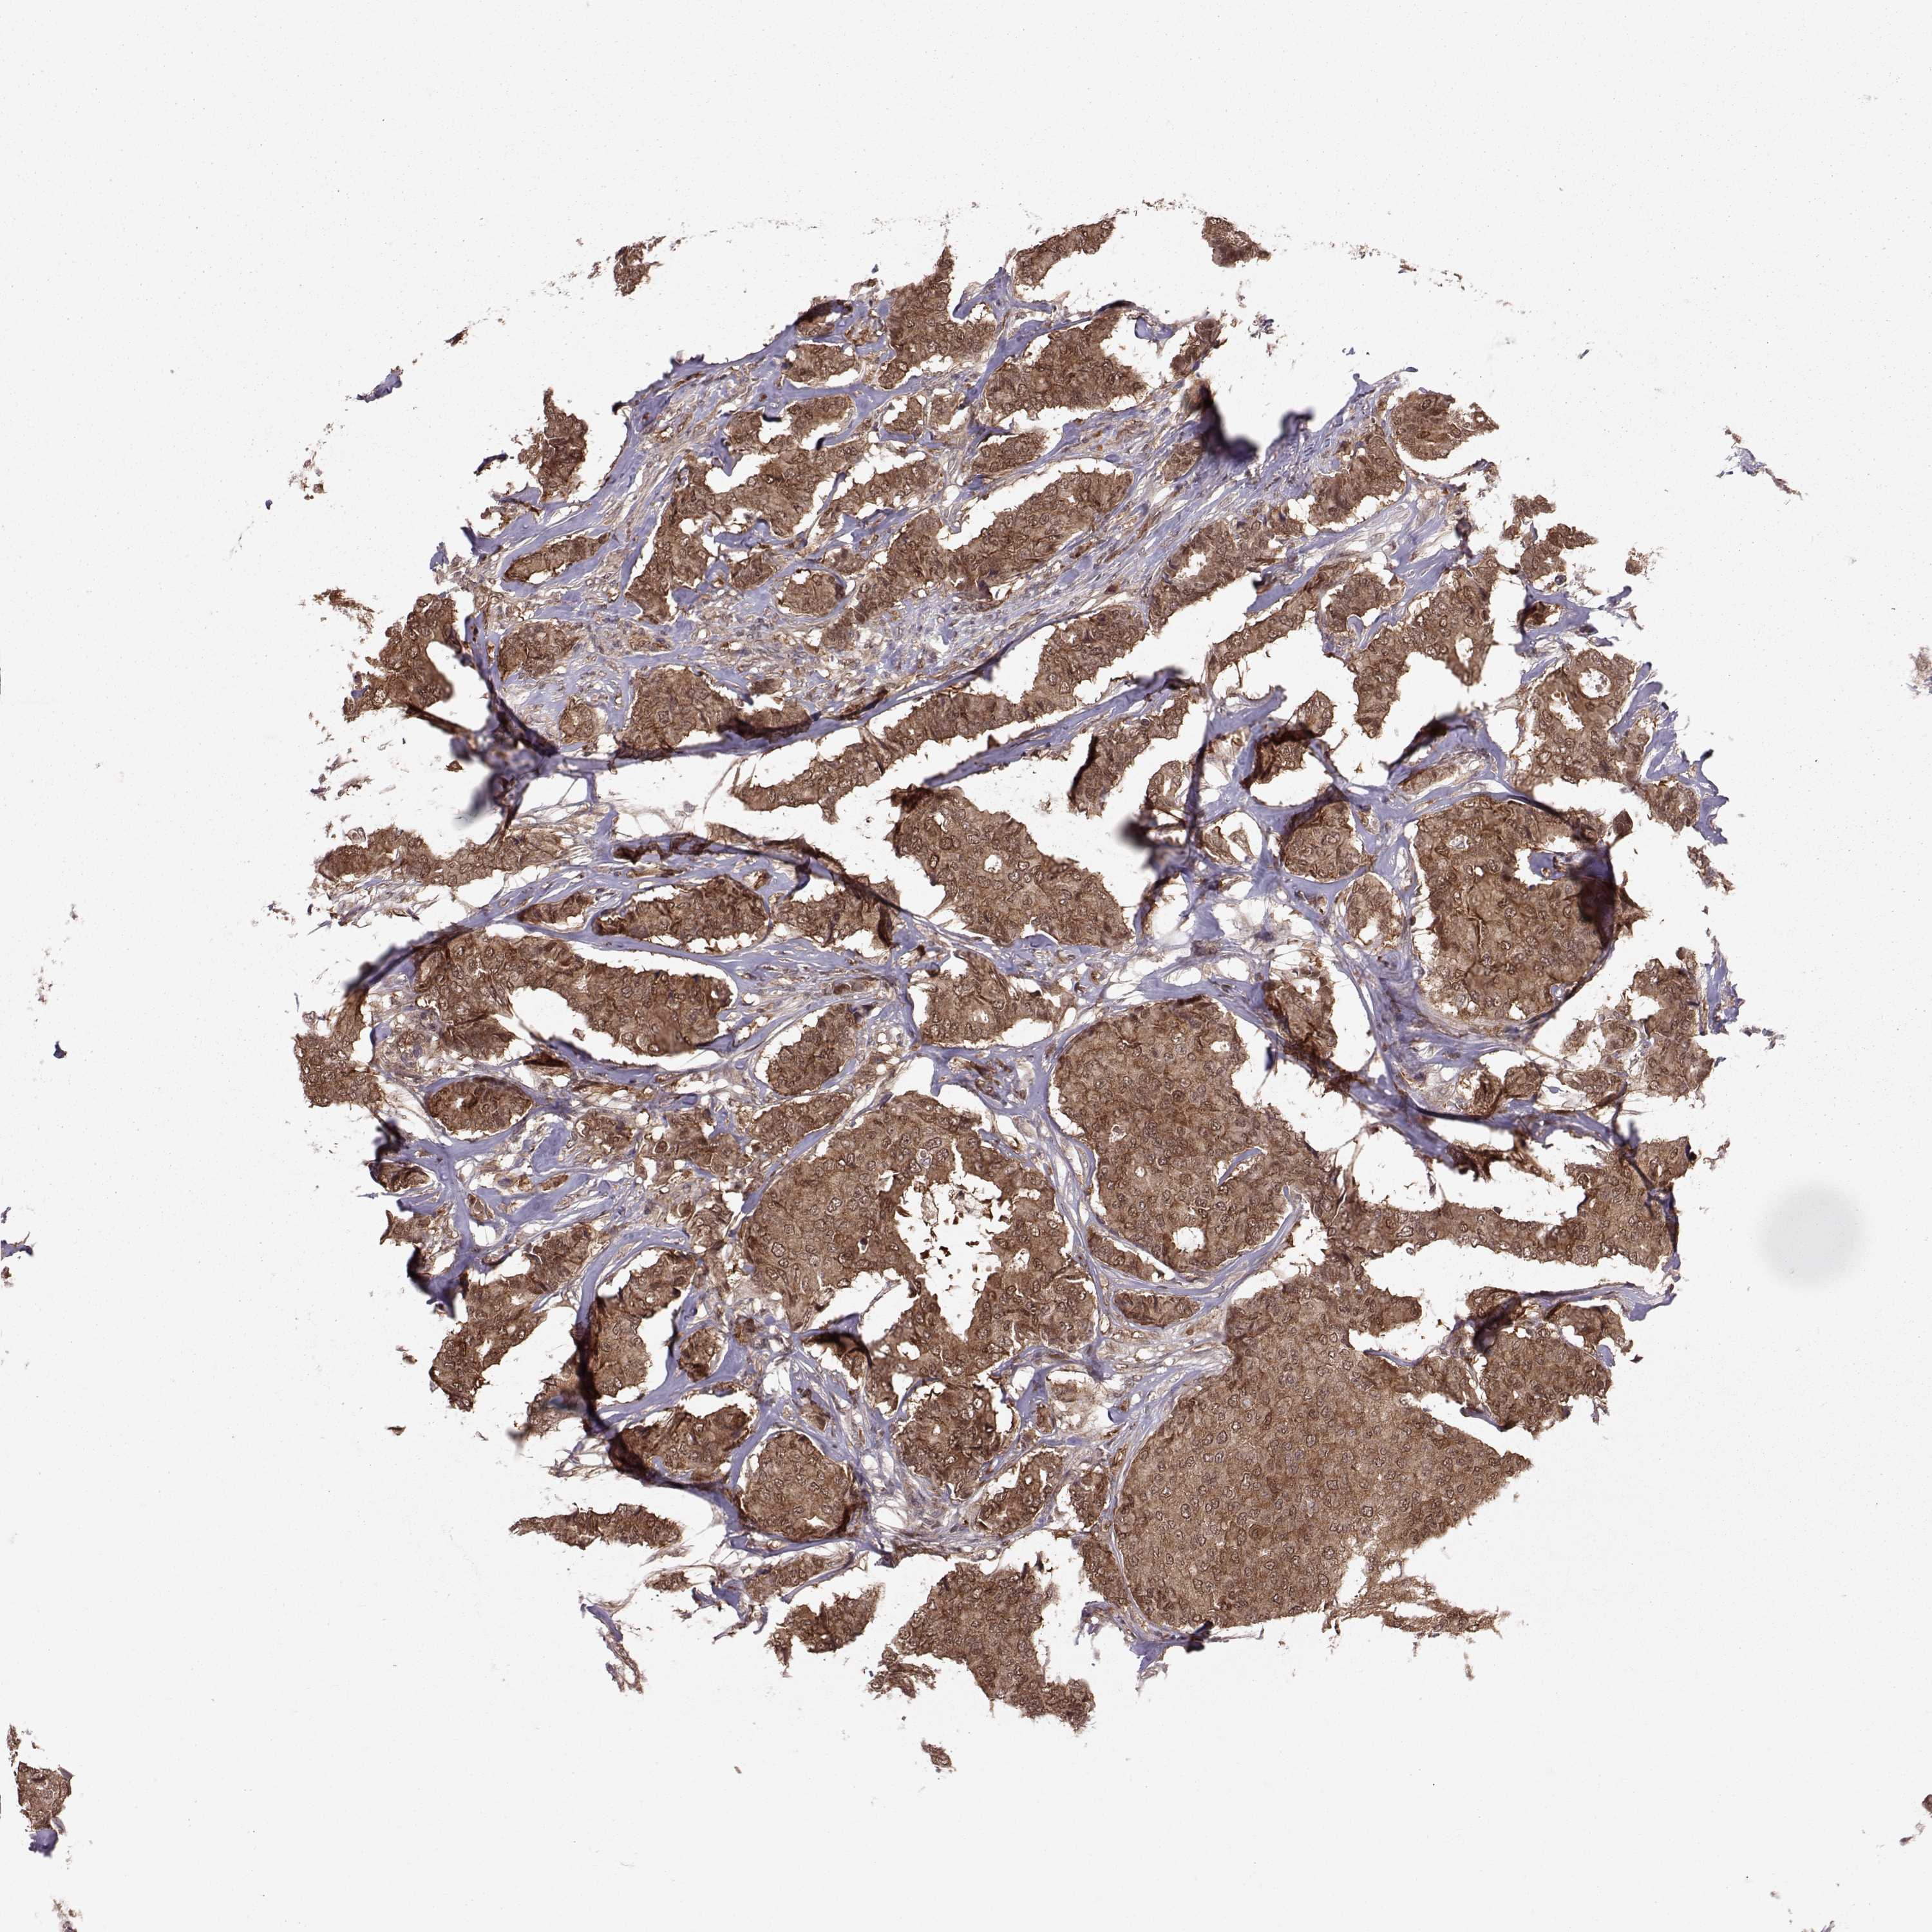

CANCER BREAST CANCER Show tissue menu

BRCA TCGA BRCA VALIDATION PROTEIN EXPRESSION